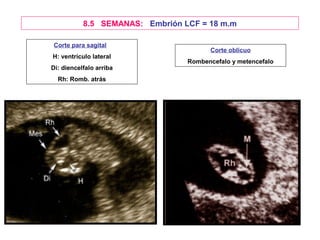

8.5 SEMANAS: Embrión LCF = 18 m.m

Corte para sagital

Corte oblicuo

H: ventrículo lateral

Rombencefalo y metencefalo

Di: diencelfalo arriba

Rh: Romb. atrás